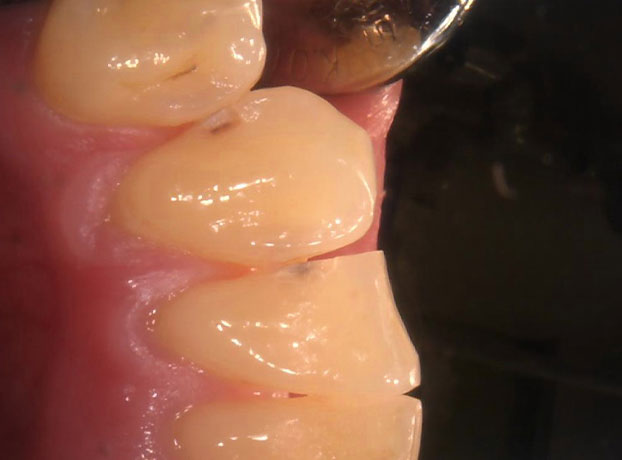

(主訴)痛みはないが虫歯がある

50代男性

前歯の歯と歯の接触部の虫歯を、ピンポイントで虫歯だけ除去して保険治療にてCR(コンポジットレジン)を詰めました。

保険診療で、余分に歯を削らずに虫歯を除去し、治療後見た目も綺麗になりました。